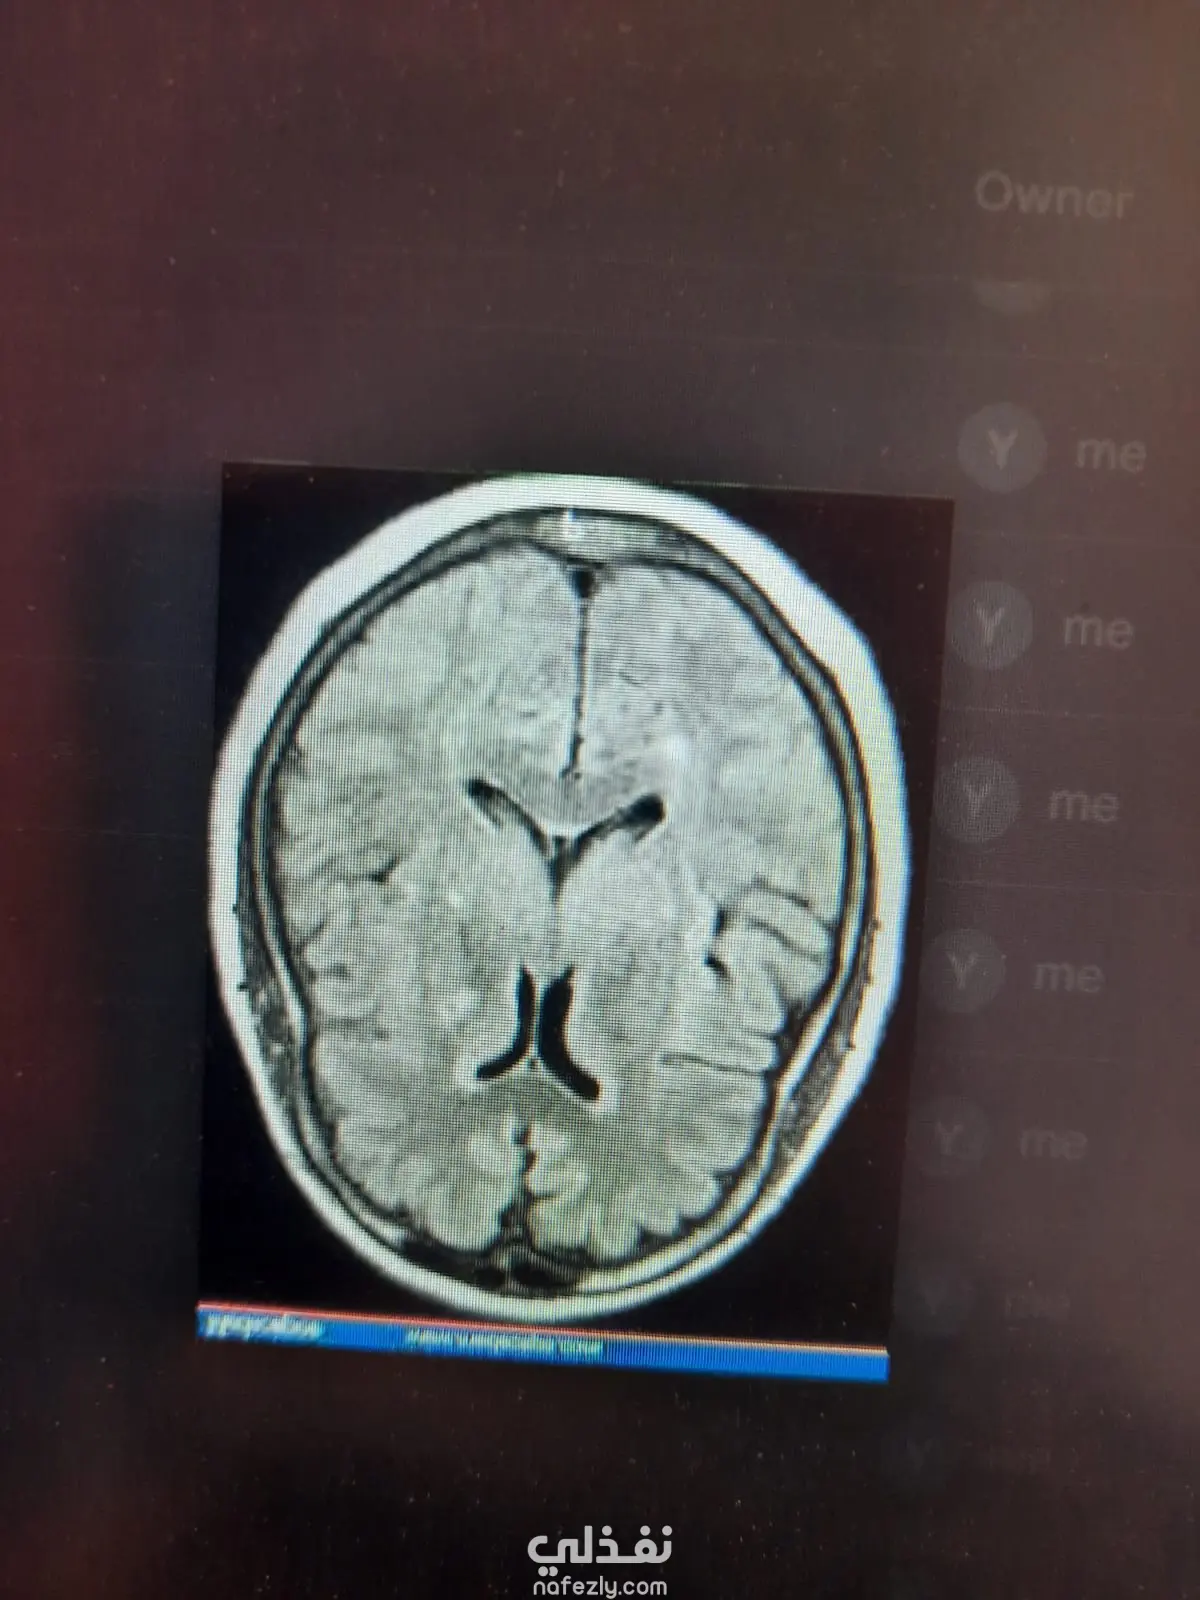

قمت بتطوير نموذج تعلم آلي للتنبؤ بوجود أورام في الدماغ باستخدام صور الرنين المغناطيسي (MRI). شمل المشروع معالجة الصور وتحويلها إلى بيانات قابلة للتحليل، ثم تدريب نموذج تصنيف للتفرقة بين الصور التي تحتوي على ورم وتلك التي لا تحتوي عليه. استخدمت تقنيات معالجة البيانات وتحليلها لتحسين أداء النموذج وزيادة دقته في التنبؤ. يهدف المشروع إلى توظيف تقنيات الذكاء الاصطناعي للمساعدة في الكشف المبكر عن أورام الدماغ ودعم عملية التشخيص الطبي.